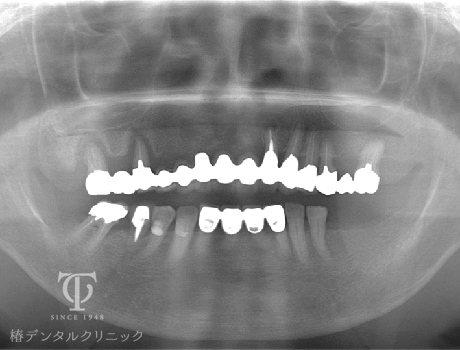

術前レントゲン

インプラント治療後レントゲン